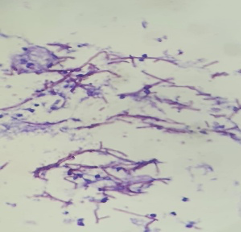

A 52 year old male was clinically diagnosed with a space-occupying lesion in the left parietal lobe of brain. Squash and other smears were made .3 images are shown, make you diagnosis and why?